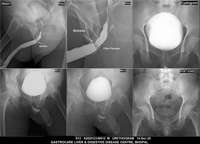

Section: URETHROGRAM Total: 95 images

BaM Enteroclysis Loopogram BaE Fistulogram Urethrogram HSG